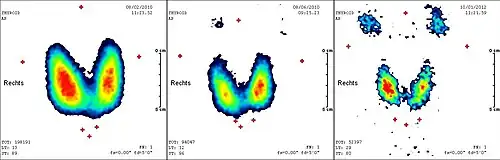

In den meisten Fällen tritt die vollständige Wirkung der Radiojodtherapie in den ersten drei bis sechs Monaten ein, so dass nach diesem Zeitraum eine abschließende Untersuchung zur Beurteilung des Therapieeffektes und -erfolges ansteht. Diese umfasst üblicherweise neben der Bestimmung der Schilddrüsenhormone auch ein Schilddrüsen-Sonogramm und ein -Szintigramm. Da in einem Teil der Fälle auch nach sechs Monaten noch eine gewisse Spätwirkung der Radiojodtherapie zu erwarten ist, soll die Indikation zu einer Wiederholung der Behandlung nicht zu früh gestellt werden.

Einige Tage nach der Therapie wird ein Ganzkörperszintigramm angefertigt. Die Therapie wird in etwa dreimonatigen Abständen wiederholt, bis weder das Szintigramm, das Ultraschallbild der Halsregion, noch der Tumormarker Thyreoglobulin einen Hinweis auf nennenswertes verbliebenes Schilddrüsengewebe (gutartig oder bösartig) geben. Eine Gesamt-Aktivität über alle durchgeführten Radiojodbehandlungen von bis zu 74 GBq (2000 mCi) wird bei sonst gesunden Patienten meist problemlos vertragen. Bei höherliegenden Aktivitäten ist mit einem erhöhten Risiko für eine dauerhafte Schädigung des Knochenmarks als blutbildendes Organ zu rechnen.